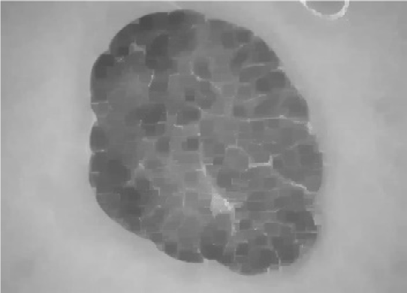

图1

使用大小为 7×7的非锐化滤波器的所提方法步骤:(A) 原始ISIC_0010447皮肤镜图像,(B) 去毛预处理后的图像,(C) 预处理图像的灰度版本,(D) 第一次迭代后的首个中性版本,(E)–(H) 最后一次迭代后的中性映射算子,分别为 (E) 最终真值图像T;(F) 最终不确定图像I;(G) 最终假值图像F;(H) 最终中性版本,(I) 输出的中性图像,(J) K均值聚类图像(无监督分割图像)。

图1展示了使用大小为 7×7的非锐化掩模滤波器进行中性映射时各阶段的相应图像。图1D显示了首先生成三个子集T, F,和I的皮肤镜中性图像,在第一次迭代后所示,其中在下一次迭代之前计算了熵值。随后,创建了这三个子集,并计算其熵值,与先前获得的熵值进行比较。此过程反复执行,直到最近一次迭代的熵值与其先前熵值之间的差异除以前一个熵值小于 α optimal¼ 0.0014,即

满足条件,则终止迭代过程,并得到NS图像的最终T、F和I算子,如图1E–H所示。T, F, 和 I算子的中性集图像结果如图1E–H所示。